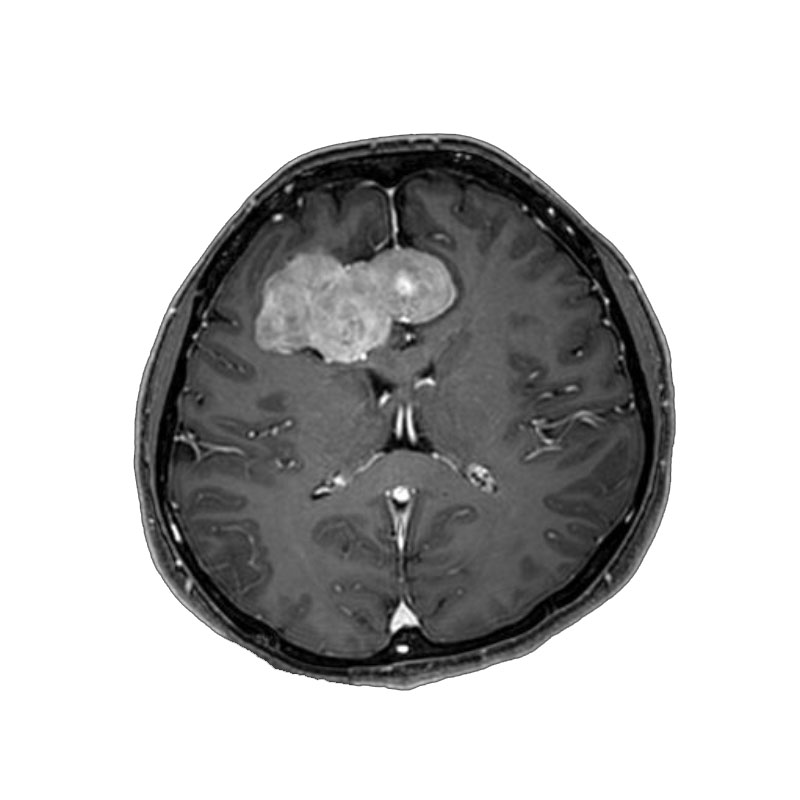

脳室内腫瘍

摘出術

北野/濵田